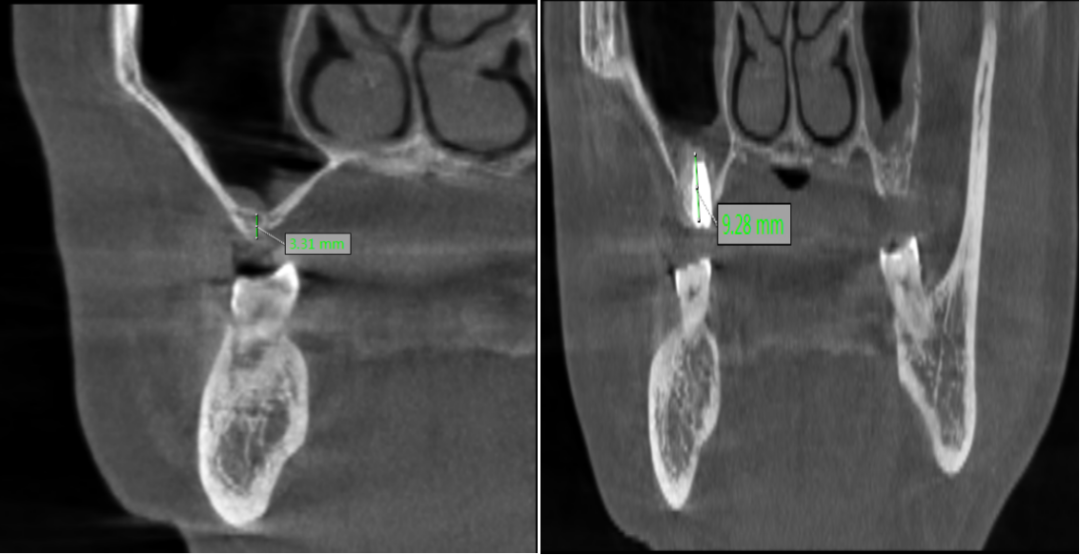

种植牙成功的核心在于充足的骨量支撑,对于骨量严重不足的患者,术前精准评估与科学规划非常重要。口腔科闫慧鑫主任带领团队,结合患者全身健康状况、口腔功能需求及美学期待,运用三维 CBCT 影像技术对颌骨进行全方位、立体化扫描分析。通过精准测量剩余牙槽骨的高度、宽度,明确上颌窦位置与形态,同时模拟手术全过程与修复效果,最终为患者制定了上颌窦外提升同期种植体植入的个性化手术方案,让每一份骨量都能得到充分利用。